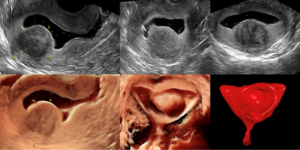

הערכת חלל הרחם באולטרהסאונד (2D&3D Ultrasound, SIS)

אולטרהסאונד דו ממדי (2D Ultrasound) בגישה וגינלית ובתוספת דופלר (Doppler Ultrasound) ותלת מימד (3D Ultrasound) מאפשר להעריך בצורה טובה את רירית וקיר הרחם כמו גם השחלות ולבצע בדיקת AFC. טכנולוגיה זו מאפשרת גילוי של מומי רחם מולדים, שרירנים וציסטות ברמת דיוק גבוהה. רמת הדיוק לוקה בחסר כאשר מדובר בפוליפים של רירית הרחם והידבקויות תוך רחמיות. הזלפת נוזל פיזיולוגי (סליין) לחלל הרחם בעזרת צנתר (קטטר) ובצוע

אולטרהסאונד דו ממדי (2D Saline Infusion Sonography – SIS) מעלה את שיעור האבחון של פוליפים והידבקויות תוך רחמיות ל90%, שיעור דומה לזה המתקבל בהיסטרוסקופיה. הוספה של תלת מימד לחלל הרחם לאחר הזלפת הנוזל סליין לחלל (3D Saline Infusion Sonography) נחשבת אף טובה יותר מהיסטרוסקופיה מאחר ומאפשרת להעריך את חלל הרחם וקיר הרחם ביחד בשלושה מישורים.